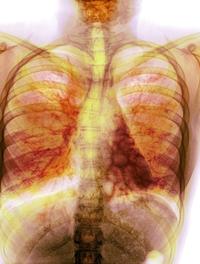

Le cancer bronchique non à petites cellules (CBNPC) est souvent découvert tardivement. A l’heure actuelle, l’indication d’une résection [...]

Le cancer bronchique non à petites cellules (CBNPC) dans sa variété épidermoïde représente 20 à 30 % de tous les cancers bronchiques. [...]

La surveillance scannographique après chirurgie dans le cancer bronchique non à petite cellule repose davantage sur des avis d’experts [...]

L’immunothérapie est indiquée dans les cancers bronchiques non à petites cellules (CNPC) depuis quelques temps maintenant, ce qui permet [...]

Environ un tiers des cancers bronchiques non à petites cellules (CBNPC) sont découverts en stade III, non résécables. Le standard thérapeutique [...]

Le cancer pulmonaire de stade III reste de pronostic très sévère. Pour les cancers de stade IIIA/N2, plusieurs schémas thérapeutiques [...]

L’une des caractéristiques du cancer et notamment du cancer bronchique est sa capacité à contourner la réponse immunitaire. PD-1 (programmed [...]

De nombreux patients atteints d’un cancer du poumon sont diagnostiqués à un stade avancé de leur maladie et relèvent d’une chimiothérapie. [...]

Le cancer du poumon à petites cellules (KBP-PC) représente 13 % de l’ensemble des tumeurs malignes pulmonaires. Il est souvent découvert [...]

Le cancer du poumon est une des causes majeures de mortalité spécifique à travers le monde, le plus souvent lors d’un stade tardif [...]

Malgré quelques progrès (assez limités), le pronostic du cancer du poumon non à petites cellules (CPNPC) à un stade avancé (IIIB ou [...]

Le carcinome bronchique est la maladie tumorale la plus fréquente dans le monde. Chez les patients de stade I opérés, la survie est [...]